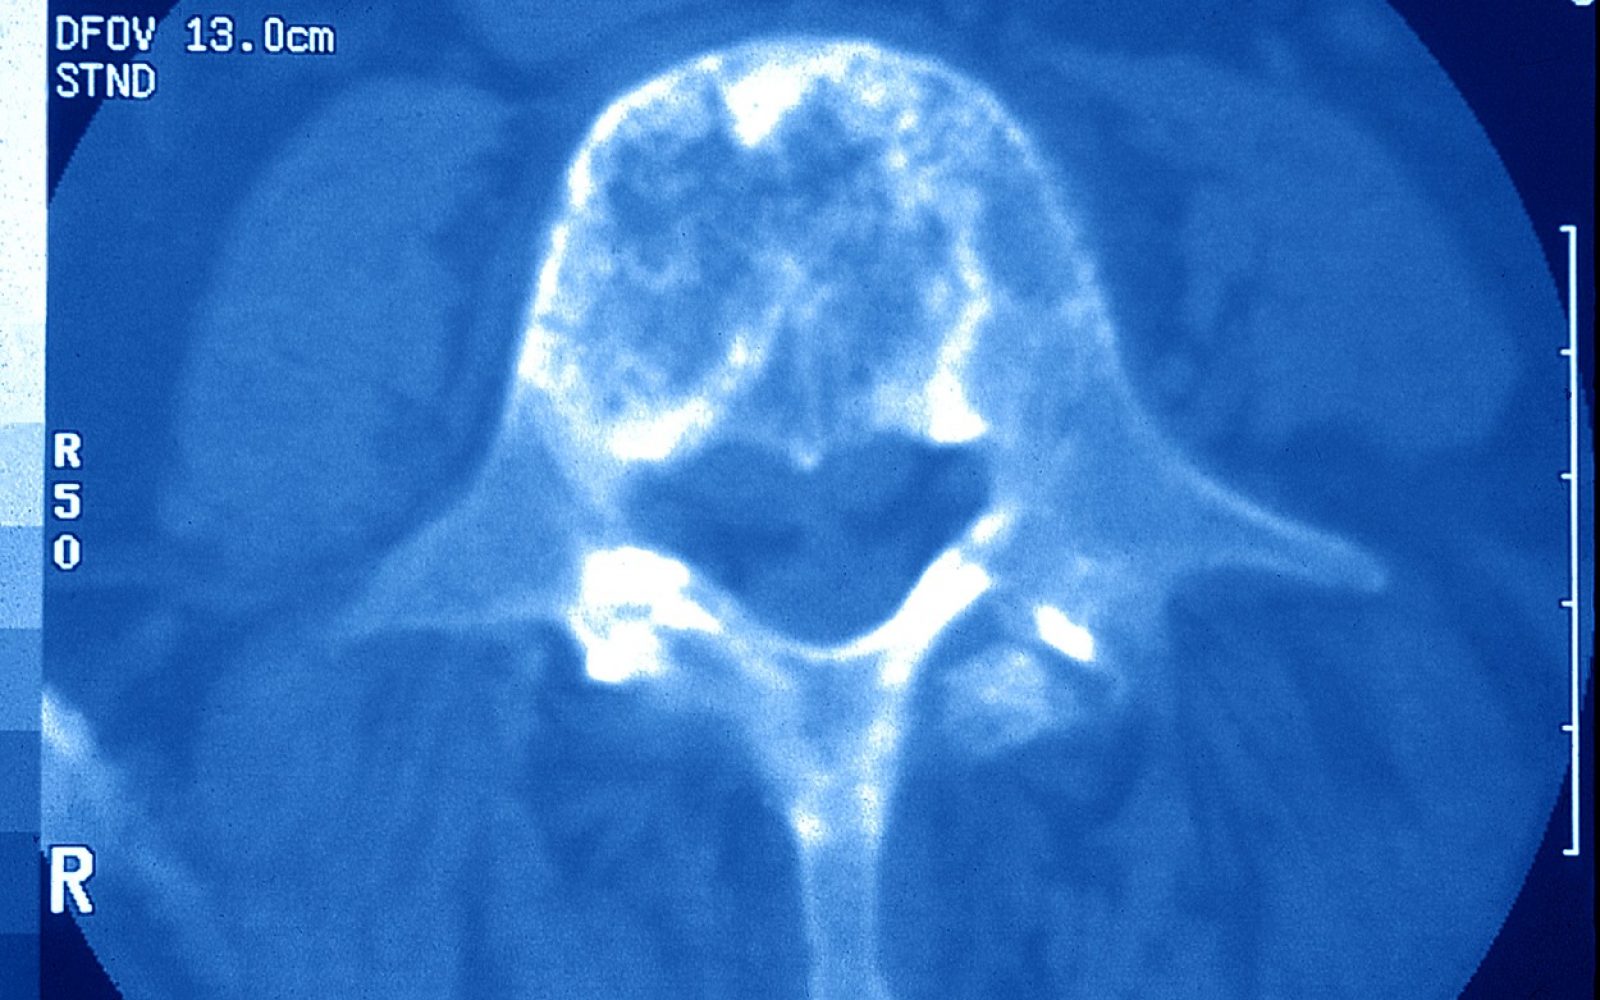

Zakaj merimo kostno gostoto?

Osteoporoza pride tiho, saj pred zlomi ne povzroča težav. Edini način, s katerim se bolezen odkrije in zdravi, je merjenje mineralne kostne gostote. Meritev je neboleča, natančna in hitro opravljena.